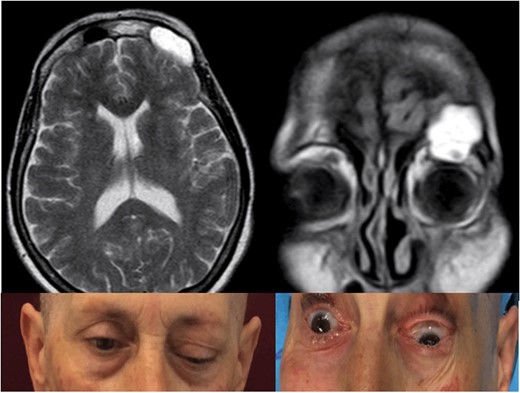

A 65-year-old female attended to our observation describing a 4-week history of left exophthalmos, which had worsened in the previous days with the association of ptosis, ophthalmoplegia and diplopia. She had no history of head trauma or previous naso-sinusal surgery. A MRI and a CT of the skull revealed a hyperintense lesion on T2-weighted images occupying the left frontal sinus that partially eroded the orbital roof and the frontal posterior wall of the sinus, with invasion of the left orbit and displacement of the ocular globe and intracranial extension without dural infiltration (Fig. 1).

Pre-operative T2-weighted MRi showing a frontal sinus mucocele with intraorbital and intracranial extension, causing ptosis, exophtalmus and diplopia.